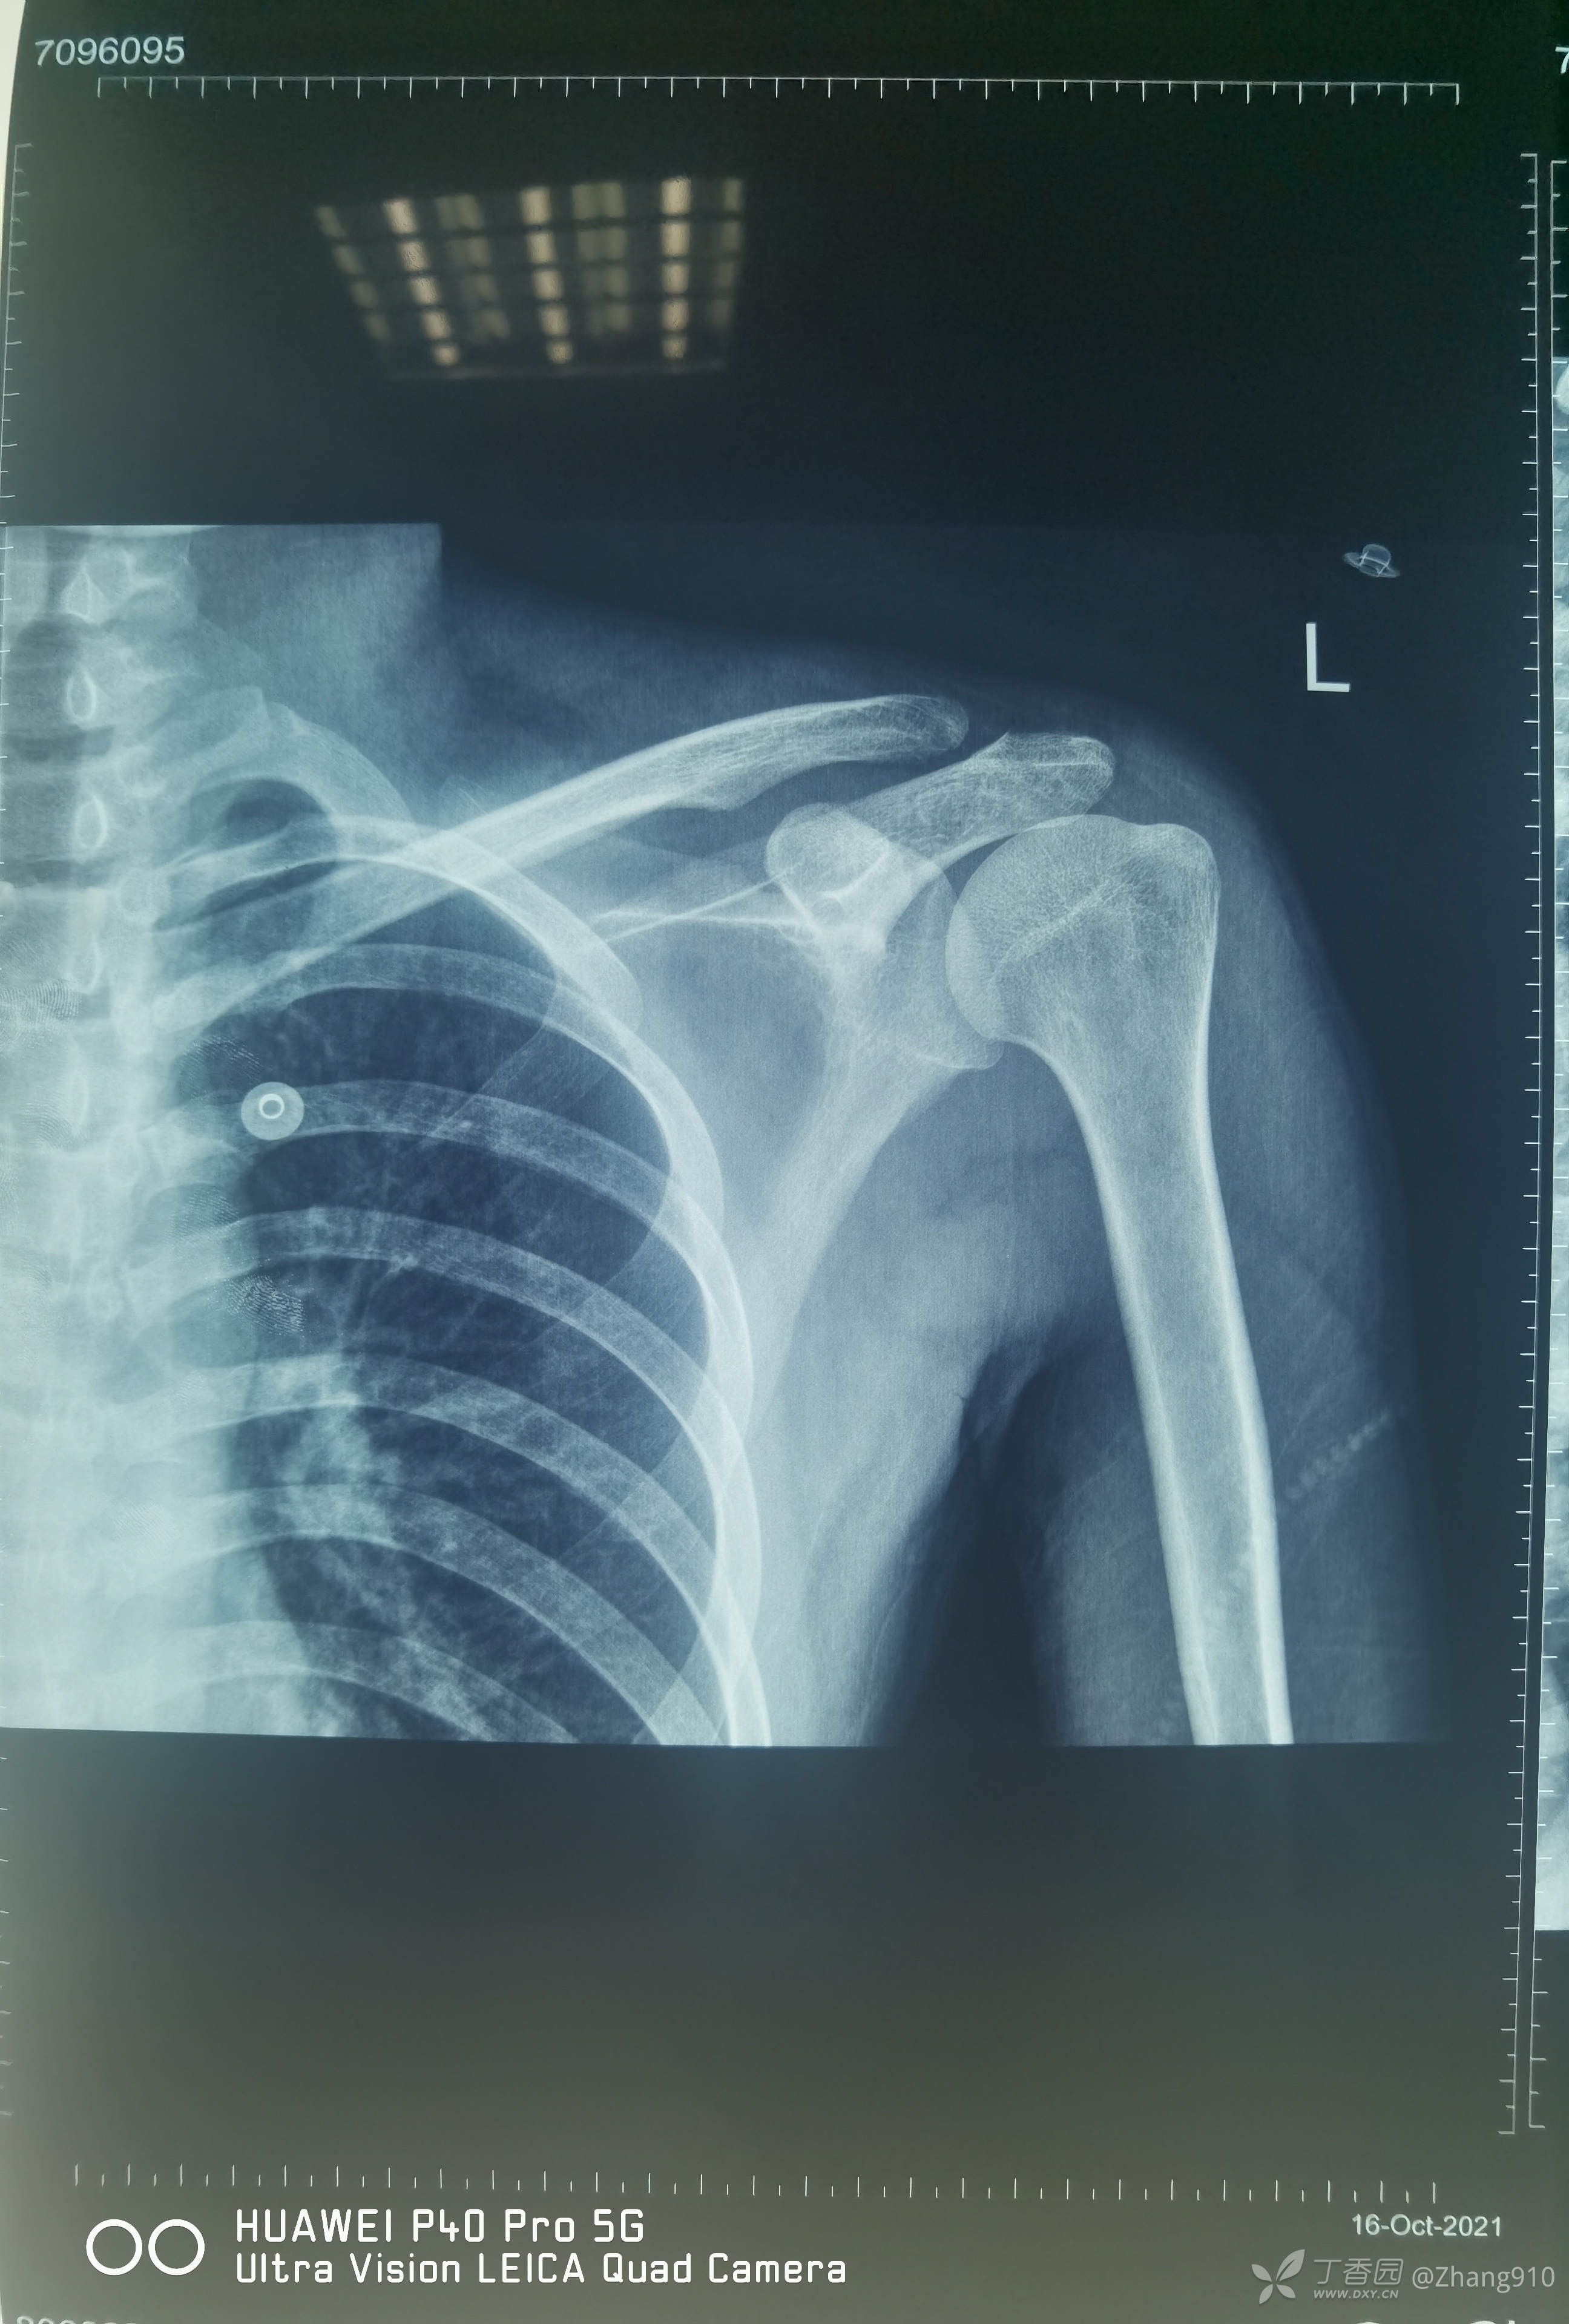

辅助检查:

X线显示:第3、5掌骨骨折

肩关节核磁共振: